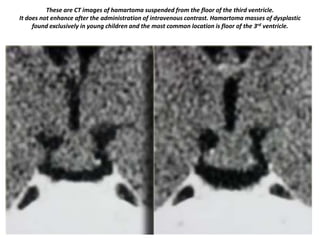

These are CT images of hamartoma suspended from the floor of the third ventricle.

It does not enhance after the administration of intravenous contrast. Hamartoma masses of dysplastic

found exclusively in young children and the most common location is floor of the 3rd ventricle.